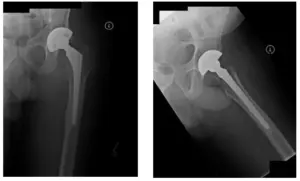

Revisión de THA izquierda realizada en 2011.

Radiografía de pelvis durante la operación